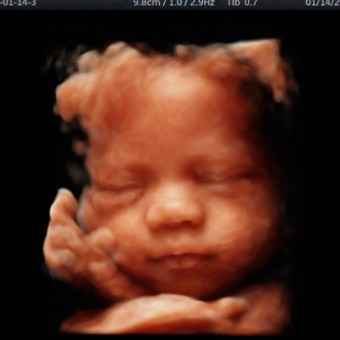

Julia's Baby Registry

Julia & Ronnie Holloway

We are so excited to welcome baby boy! If you’d like to give a card, we’d love a book for the baby’s library instead. Please know your presence is the most important gift of all. Thank you all🩵